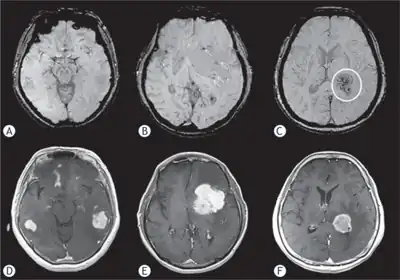

Primary central nervous system lymphoma a) Grade 1: multifocal tumors show no intratumoral susceptibility signal b) Grade 2: shows punctate low-intensity signals arrows c) Grade 3: low-intensity signals circle d,e,f) shows primary central nervous system lymphomas with intense enhancement

MRI or contrast enhanced CT classically shows multiple ring-enhancing lesions in the deep white matter. The major differential diagnosis (based on imaging) is cerebral toxoplasmosis, which is also prevalent in AIDS patients and also presents with a ring-enhanced lesion, although toxoplasmosis generally presents with more lesions and the contrast enhancement is typically more pronounced. Imaging techniques cannot distinguish the two conditions with certainty, and cannot exclude other diagnoses. Thus, patients undergo a brain biopsy or vitreous biopsy, if there is intraocular involvement.[11]